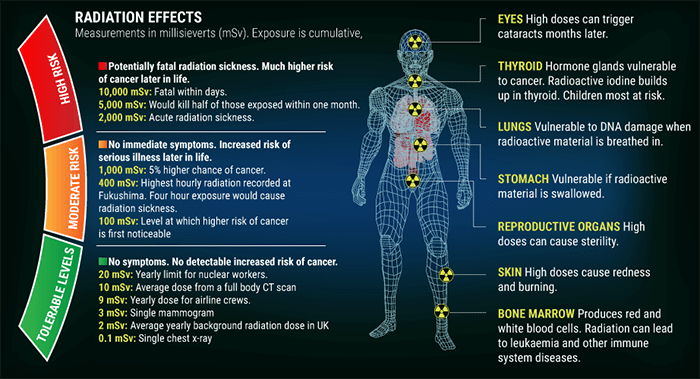

Ionizing radiation damages DNA and has harmful effects on human tissues. Therefore, we will now present the effects of radiation on the patient and provide some practical tips that can help the technologist in reducing the patient dose.

As we mentioned earlier, ionizing radiation damages DNA and has harmful effects on human tissues. These effects can be classified into stochastic and non stochastic effects.

Stochastic effects occur in a linear manner; this risk of injury increases as the dose increases, and the effects are cumulative. They occur by chance with a probability proportional to the dose, and a severity independent of the dose. The most significant risk is cancer.

Non stochastic effects are the same as deterministic effects. They are those for which incidence and severity depends on dose. In fact, after a certain threshold has been met, non stochastic effects occur.

This threshold is the limit at which the organ will be damaged with a polynomial function response.

Exposure to very high levels of radiation, such as being close to an atomic blast, can cause acute health effects such as skin burns and acute radiation syndrome (“radiation sickness”). It can also result in long-term health effects such as cancer and cardiovascular disease, if the radiation is in a moderate levels (100-1000 mSv). And finally no symptoms and no detectable risk of cancer are seen if the radiation is in tolerable level (0.1-20 mSv).

The radiation has an effect on the human organs, as we know the organs are divided into two categories the serial organs and the parallel organs. Serial Organs are organs in which disabling any subunit causes the entire organ to fail. In these organs, we have to control the maximal dose to protect all the subunits. (For example, Heart spinal cord)

Parallel Organs, are organs in which many or all of the subunits must be disabled, to cause organ failure .In these organ we have to control the mean dose of the organ, received by a percentage volume of this organ.

- The gastrointestinal tract: Radiation damage to the intestinal tract lining will cause nausea, bloody vomiting and diarrhea. This occurs when the patient exposure is 200 rems or more. The radiation will begin to destroy the cells in the body that divide rapidly. These including blood, GI tract, reproductive and hair cells, and harms their DNA and RNA of surviving cells.

- The reproductive tract: Because reproductive tract cells divide rapidly, these areas of the body can be damaged at rem levels as low as 200. Long-term, some radiation sickness patients will become sterile.